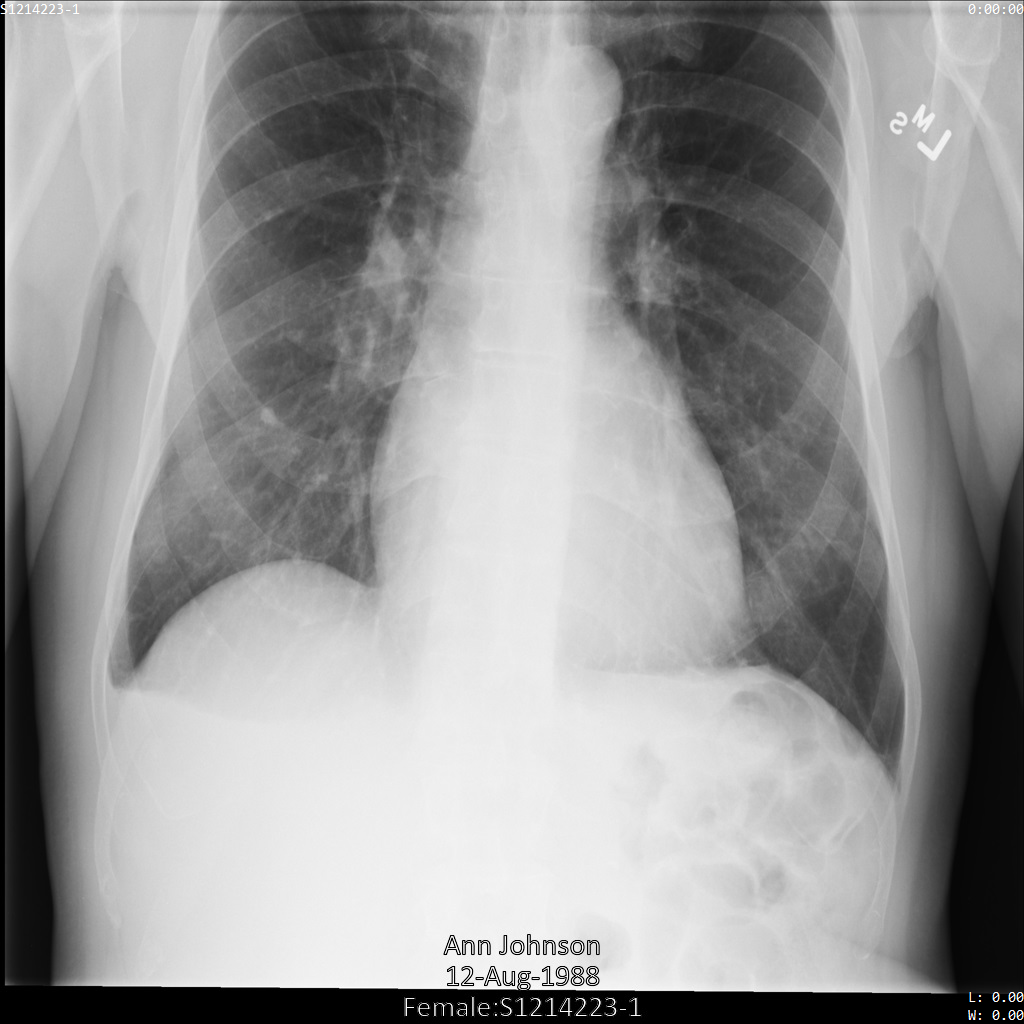

以下各部分提供的示例展示了如何使用各种方法对 DICOM 数据进行去标识化。每个示例都会提供去标识化后的图片输出。每个示例都使用以下原始图片作为其输入:

您可以将每个去标识化操作的输出图片与该原始图片进行比较,以查看该操作的效果。

将图片提交到 Cloud Healthcare API 后,图片显示如下。虽然图片顶部角落显示的元数据已被遮盖,但图片底部的烧屏受保护健康信息 (PHI) 仍然保留。如需一并移除烧屏文字,请参阅遮盖图片中的烧屏文字。